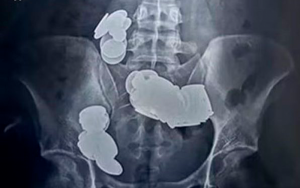

O jovem de 26 anos acreditava que ingerir moedas e ímas ajudaria na musculação (Foto: reprodução/Sir Ganga Ram Hospital)